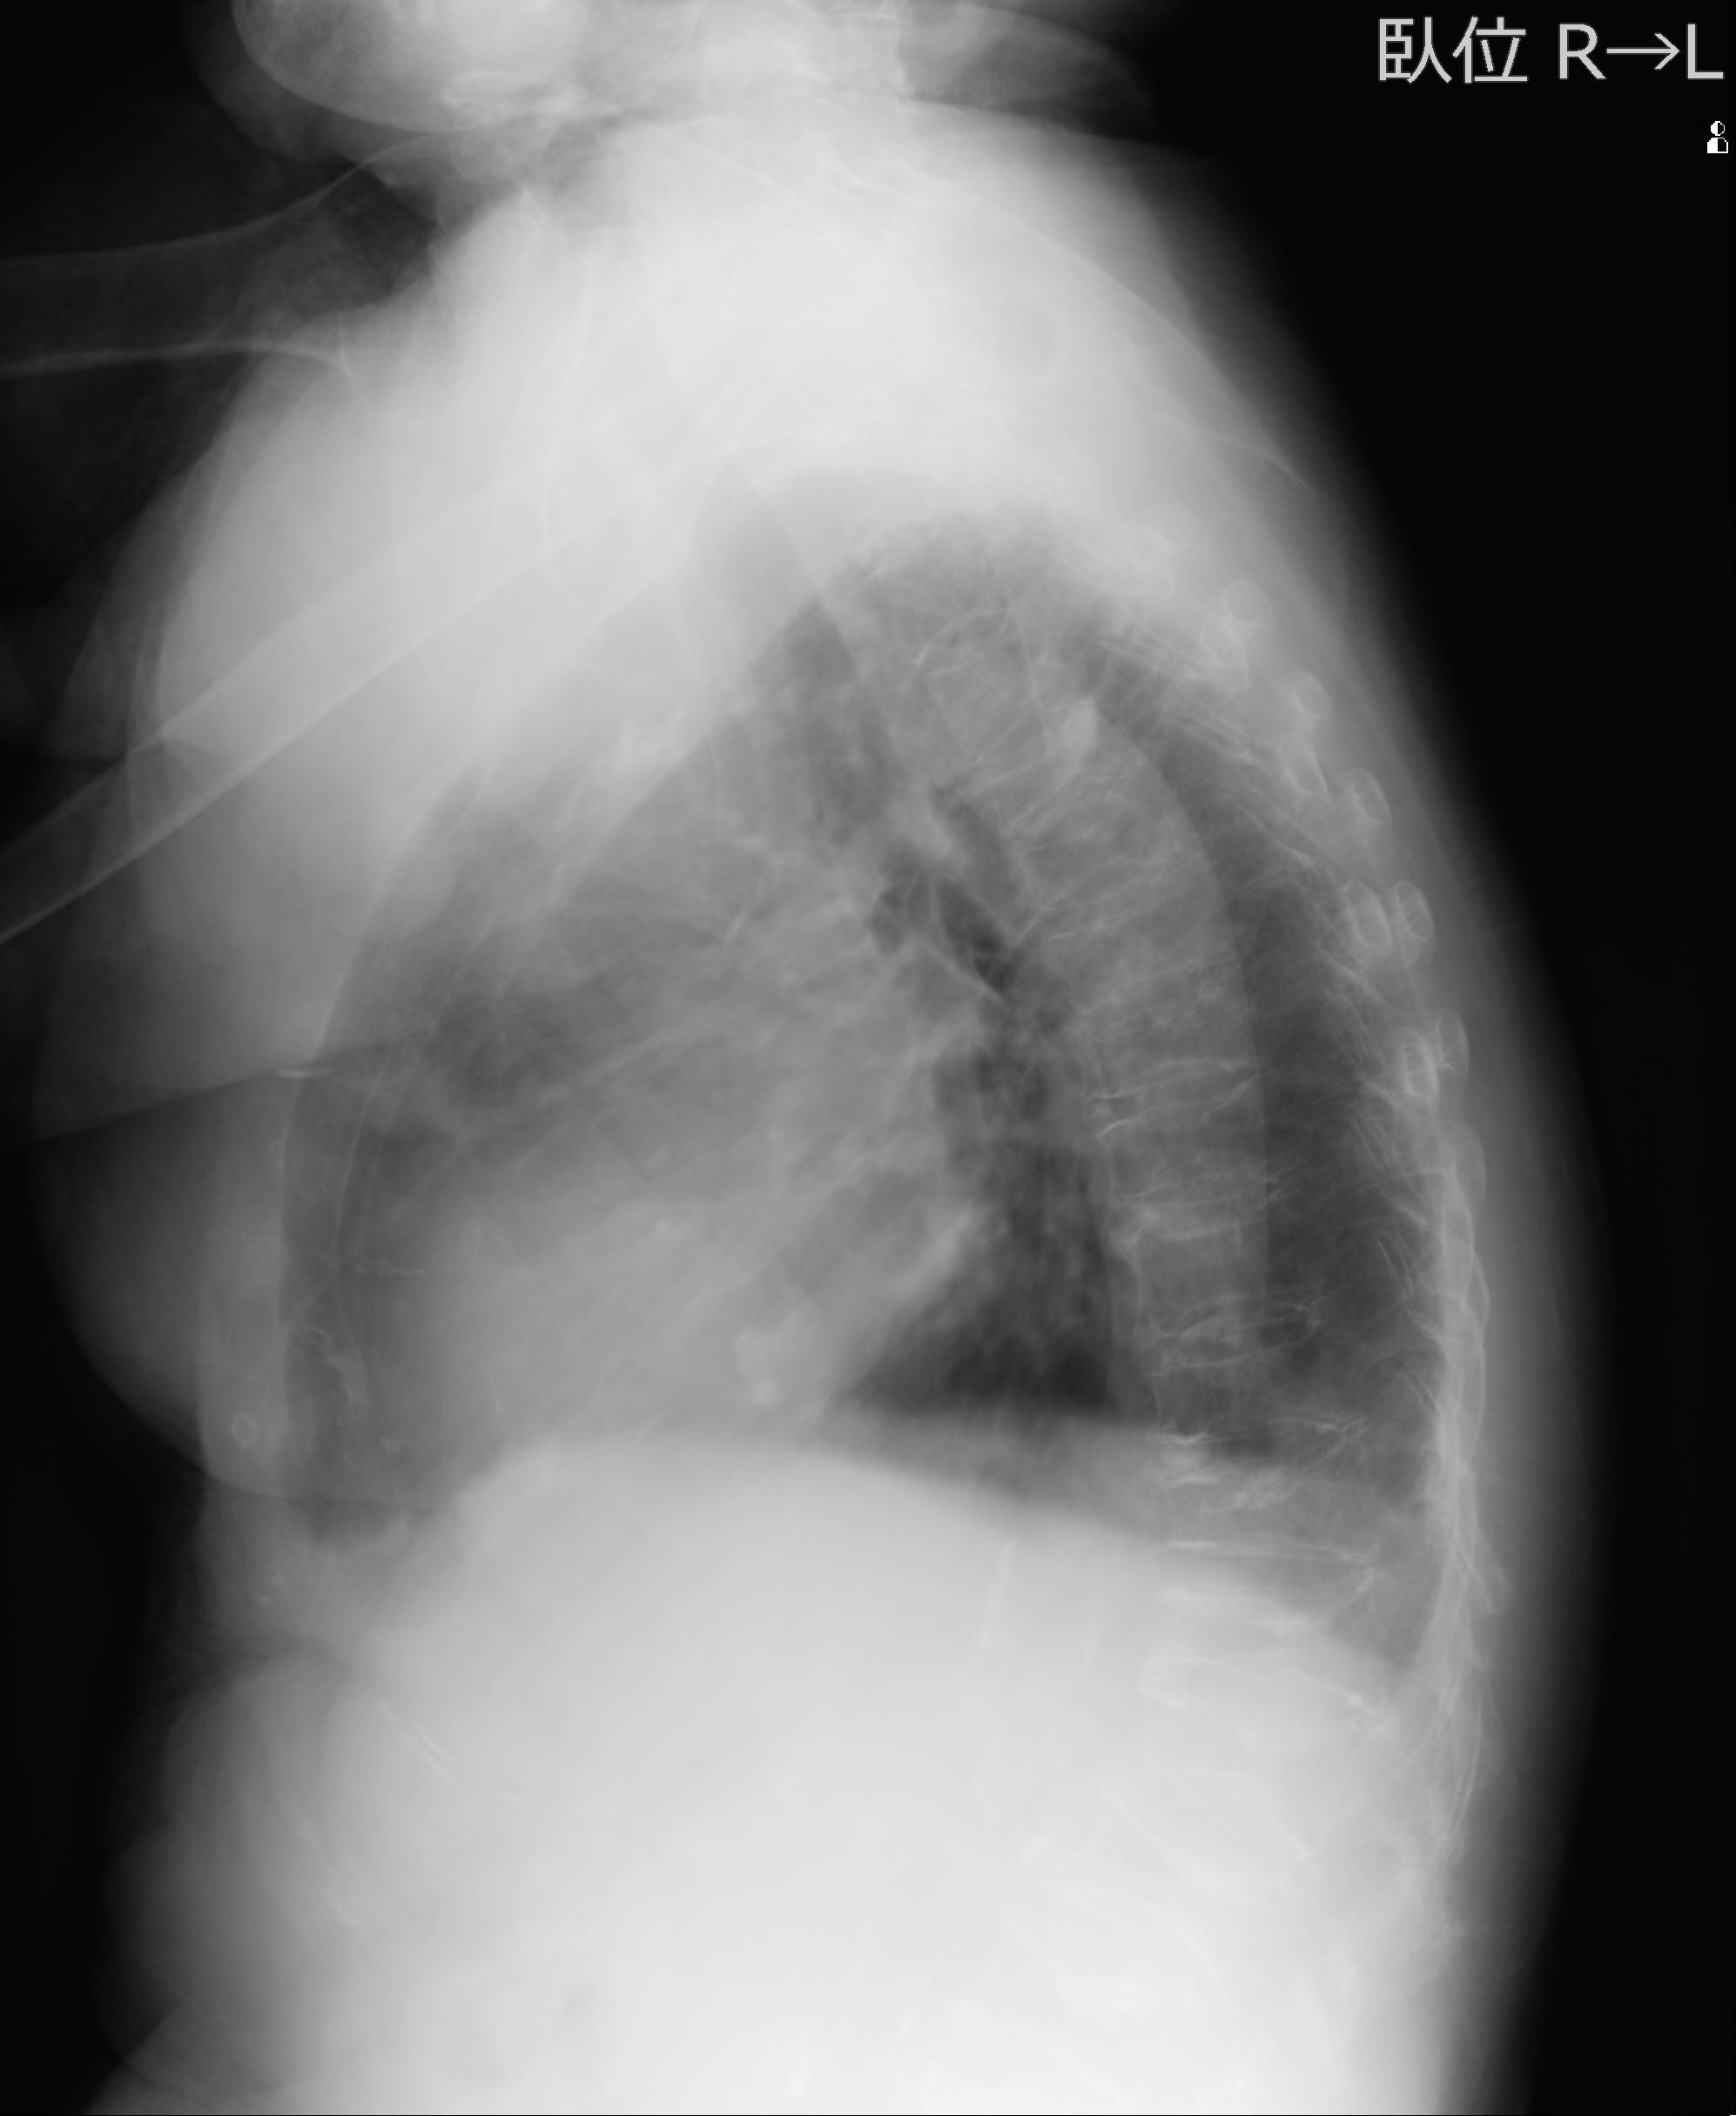

110214 12/20 肩 2R 12/21 肩 4R 72歳女性 左上腕外科頚プレート